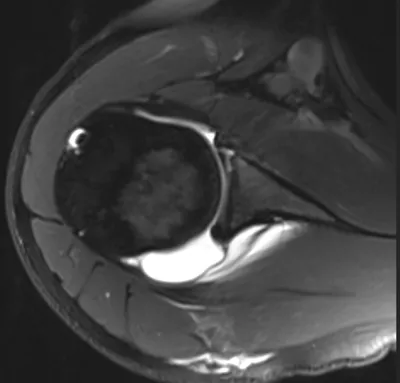

9 imagesPosterior glenoid labral tear

Arthrogram

4/11/2026